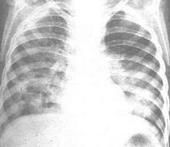

其他輔助檢查:X 線檢查顯示,肺部浸潤、縱隔增寬、胸腔積液等。